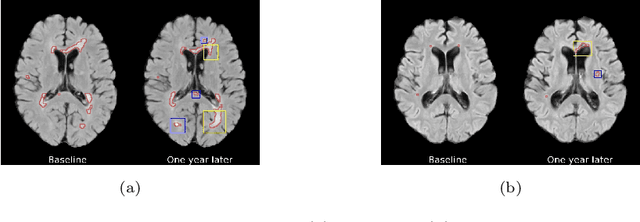

Abstract:The discovery of patient-specific imaging markers that are predictive of future disease outcomes can help us better understand individual-level heterogeneity of disease evolution. In fact, deep learning models that can provide data-driven personalized markers are much more likely to be adopted in medical practice. In this work, we demonstrate that data-driven biomarker discovery can be achieved through a counterfactual synthesis process. We show how a deep conditional generative model can be used to perturb local imaging features in baseline images that are pertinent to subject-specific future disease evolution and result in a counterfactual image that is expected to have a different future outcome. Candidate biomarkers, therefore, result from examining the set of features that are perturbed in this process. Through several experiments on a large-scale, multi-scanner, multi-center multiple sclerosis (MS) clinical trial magnetic resonance imaging (MRI) dataset of relapsing-remitting (RRMS) patients, we demonstrate that our model produces counterfactuals with changes in imaging features that reflect established clinical markers predictive of future MRI lesional activity at the population level. Additional qualitative results illustrate that our model has the potential to discover novel and subject-specific predictive markers of future activity.